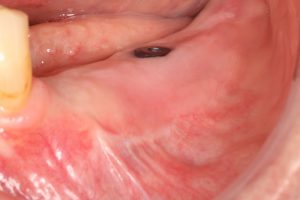

- And last but not least, Soft Tissue Management. Dealing with peri-implant tissue is mandatory to achieve long term stability of our procedures and decreasing the risk of suffering from mucositis of peri-implantitis.

There are several techniques proposed to obtain better quality tissue surrounding our implants. We know by the literature that we need at least 2.5-3mm of keratinized mucosa to have a good biological width and good implant protection.

A) Modified Kazanjian Vestibuloplasty

The classical technique created to restore the vestibule. We use it a lot of times when we have enough keratinized tissue, but we want to improve the attached mucosa. Posterior mandible or the anterior area when an overdenture is planned, are some of the regions where we indicate this procedure.

B) Free Gingival Graft

A very fast and predictable technique to obtain keratinized tissue. If less than 5 mm of keratinized mucosa is present, this procedure should be mandatory. Keratinized tissue is the seat belt of our implants.